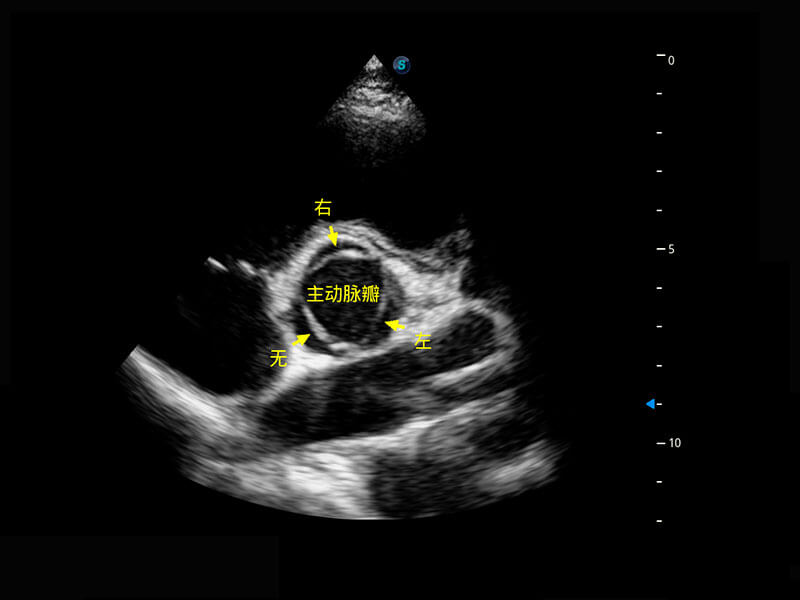

新生儿心脏